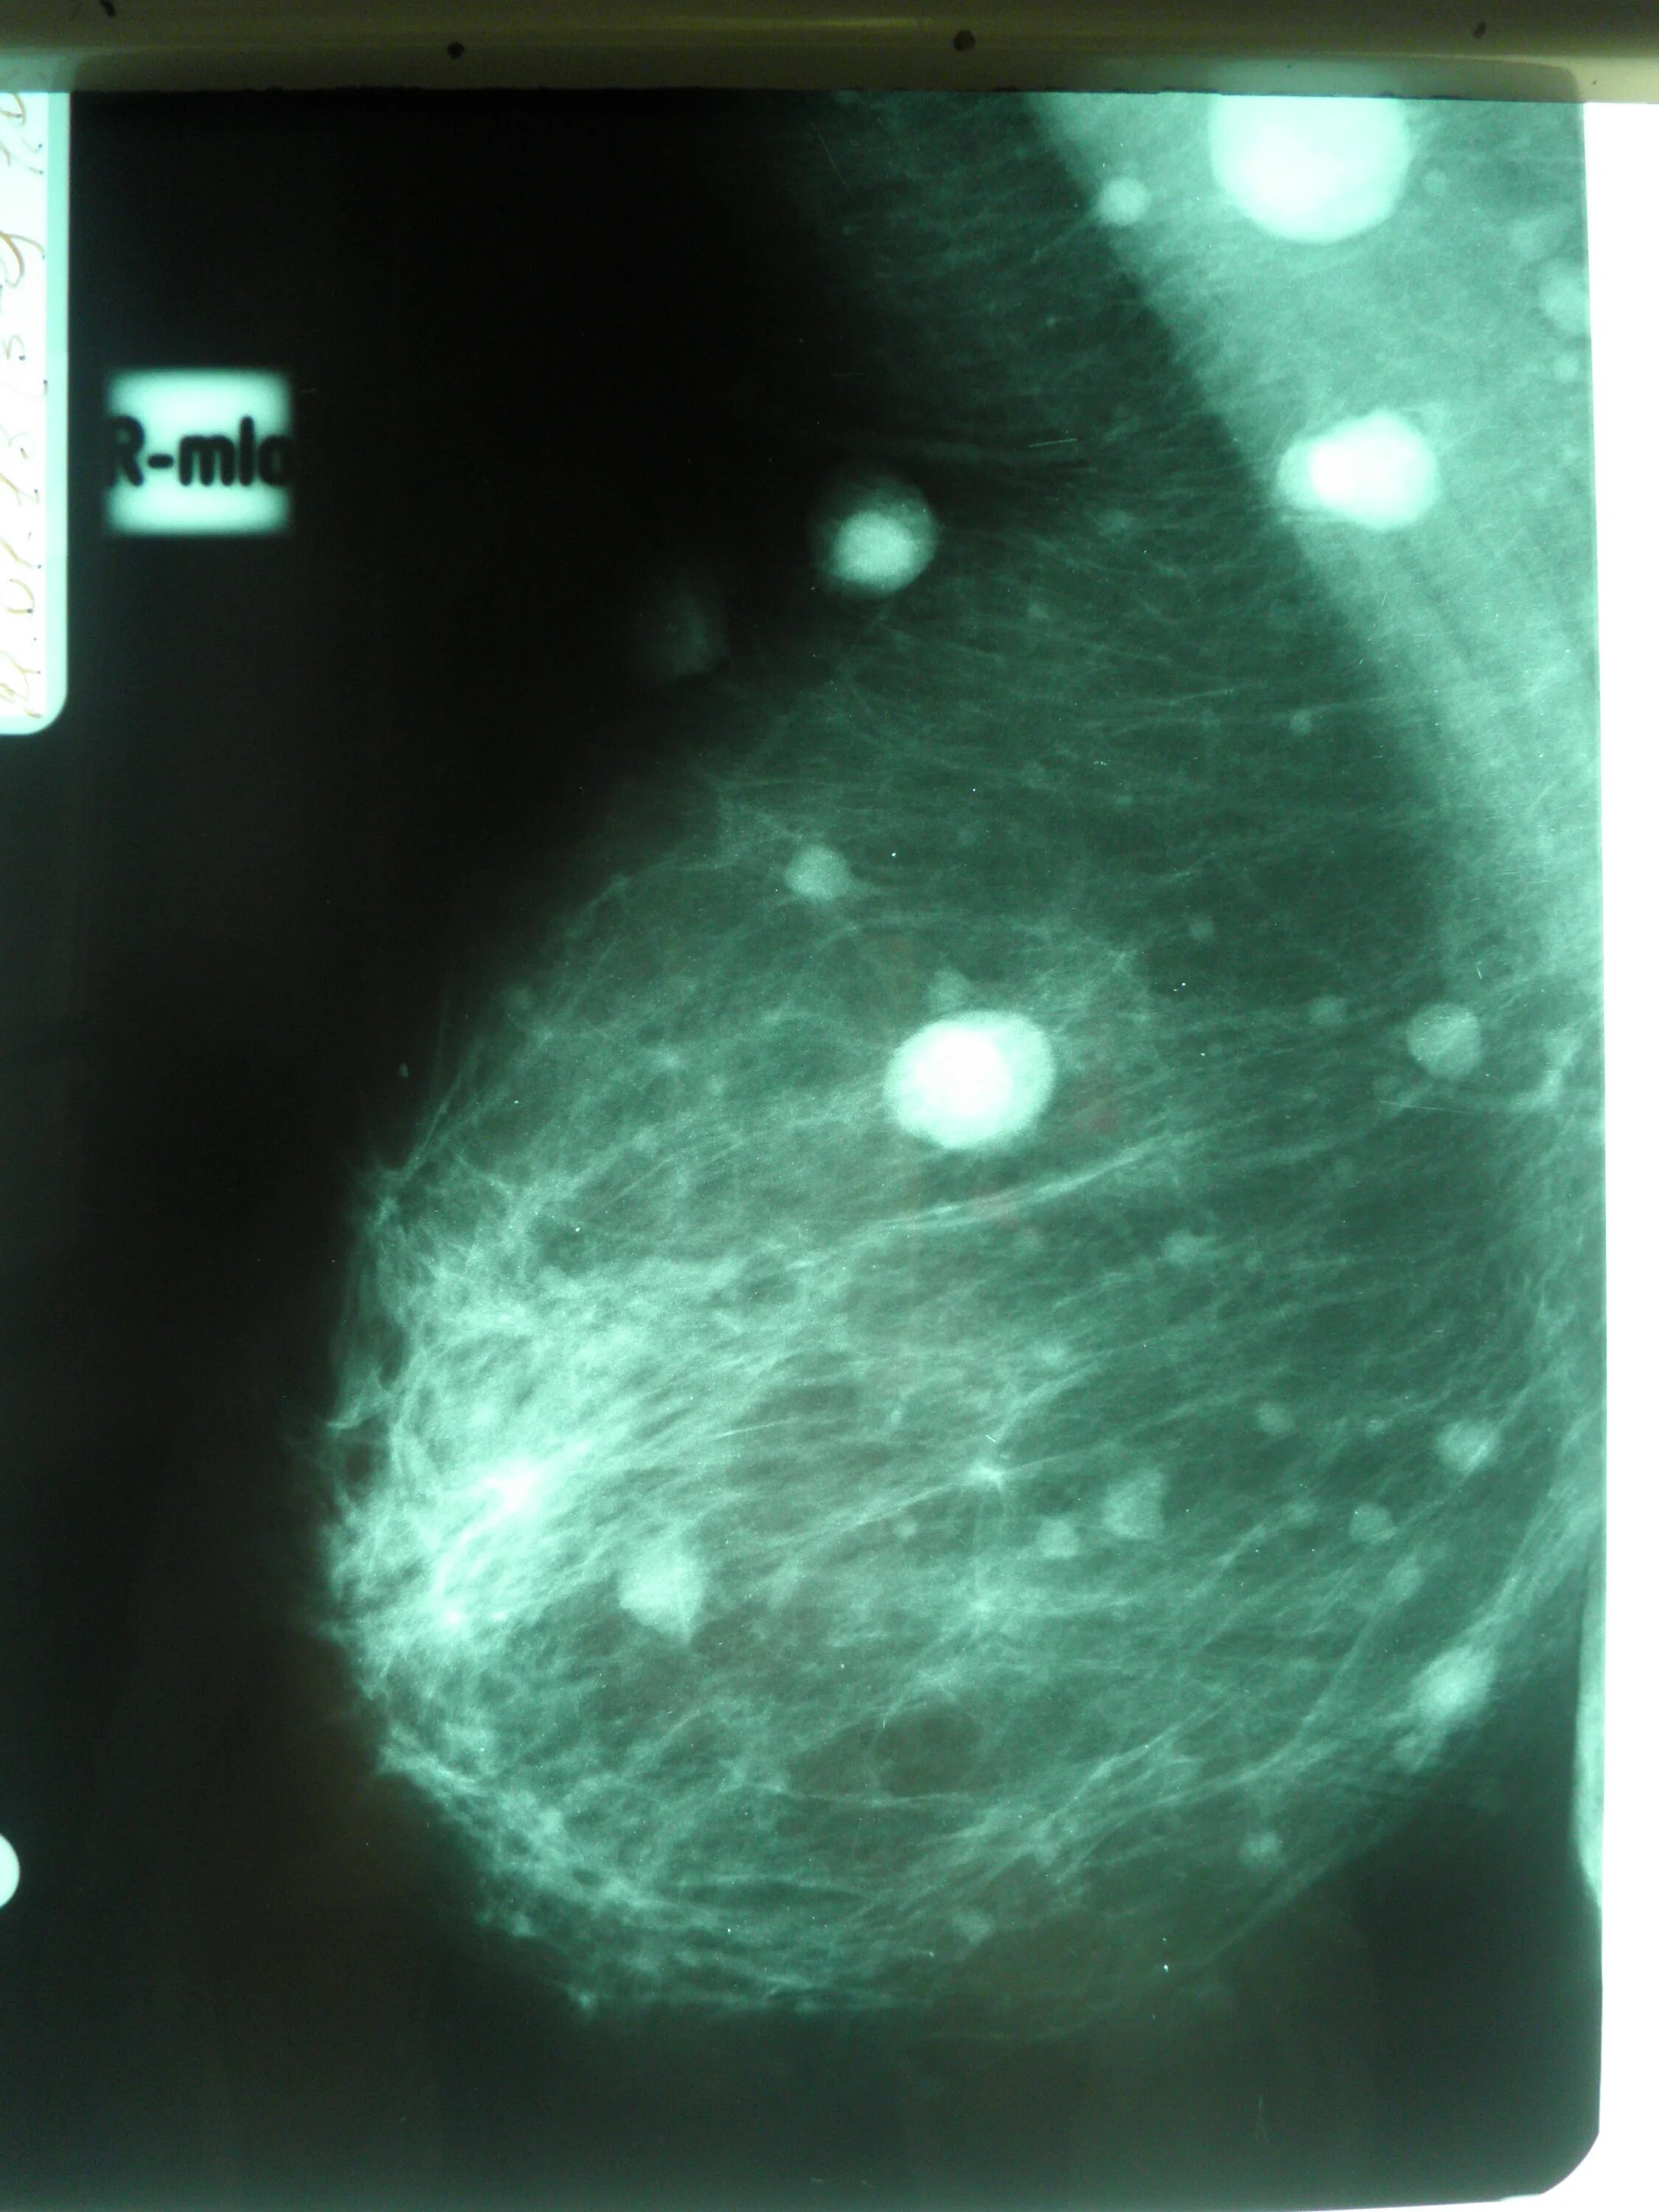

Как выглядит киста молочных желез